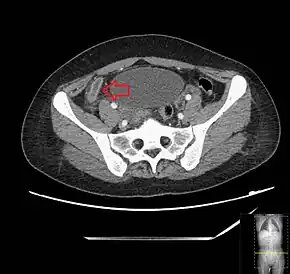

Computed tomography

Where it is readily available, computed tomography (CT) has become frequently used, especially in people whose diagnosis is not obvious on history and physical examination. Although some concerns about interpretation are identified, a 2019 Cochrane review found that the sensitivity and specificity of CT for the diagnosis of acute appendicitis in adults was high.[63] Concerns about radiation tend to limit use of CT in pregnant women and in children, especially with the increasingly widespread usage of MRI.[64][65]

The accurate diagnosis of appendicitis is multi-tiered, with the size of the appendix having the strongest positive predictive value, while indirect features can either increase or decrease sensitivity and specificity. A size of over 6 mm is both 95% sensitive and specific for appendicitis.[66]

However, because the appendix can be filled with fecal material, causing intraluminal distention, this criterion has shown limited utility in more recent meta-analyses.[67] This is as opposed to ultrasound, in which the wall of the appendix can be more easily distinguished from intraluminal feces. In such scenarios, ancillary features such as increased wall enhancement as compared to adjacent bowel and inflammation of the surrounding fat, or fat stranding, can be supportive of the diagnosis. However, their absence does not preclude it. In severe cases with perforation, an adjacent phlegmon or abscess can be seen. Dense fluid layering in the pelvis can also result, related to either pus or enteric spillage. When patients are thin or younger, the relative absence of fat can make the appendix and surrounding fat stranding difficult to see.[67]